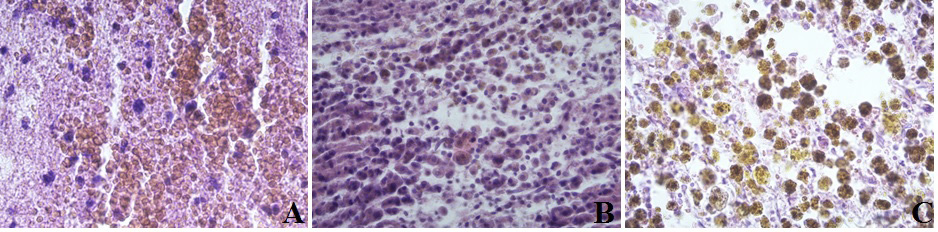

Figure 5 – Rats’ brain tissue in the hematoma area

Note: A – control group on the 1st day; B – control group on the 7th day; C – control group on the 14th day. Staining: hematoxylin and eosin; Mag. ×400

In the control group animals, on the first time a day after modeling an intracerebral hemorrhage along the periphery of the hematoma, the following disorders were detected: a pronounced edema; violation of histoarchitectonics of the neuronal layers of the cortex, pronounced ischemic changes, karyolysis of neurons, a moderately pronounced perifocal leukocyte reaction and a less pronounced glial reaction (Fig. 5A).

Polymorphism of neurons was detected: swelling of neurocytons, the nuclei of neurons were deformed and basophilic, the nucleoli were deformed and displaced to the periphery. In places, the nuclei and nucleoli were almost or completely indistinguishable. There was also neuronal karyolysis, a moderate perifocal leukocyte response and a less pronounced glial response (Fig. 5A).

On the seventh day, a moderately pronounced perifocal leukocyte reaction changed to a moderately pronounced glio-macrophage reaction with an admixture of single macrophages with an intracellular accumulation of a blood pigment (hemosiderophage) (Fig. 5B). On day 14, a moderately pronounced glio-macrophage reaction persists, but with an admixture of a few macrophages with intracellular accumulation of a blood pigment (hemosiderophages) (Fig. 5C).

When analyzing the group using etoxidol, it was established that a perifocal edema was less pronounced compared to the control group (Fig. 6A) and the group where carbamylated darbepoetin had been used (Fig. 7A); but it was more pronounced than in the group of a combined use of carbamylated darbepoetin and etoxidol (Fig. 8A). In the animals treated with carbamylated darbepoietin and a combination of drugs, the signs of an inflammatory reaction with the development of leukocyte infiltration were more pronounced. At the same time, its severity did not reach the degree of intensity recorded in the control group. On day 7, a glio-macrophage reaction in the etoxidol groups (Fig.6B) and the carbamylated darbepoetin group (Fig. 7B) was ahead of the control group. In the group of the combined use of carbamylated darbepoietin and etoxidol (Fig. 8B), more pronounced resorption processes in the form of clusters of a few macrophages accumulation of a blood pigment (hemosiderophages), were revealed. On the 14th day, the processes of resorption in the groups of etoxidol (Fig. 6C) and carbamylated darbepoetin (Fig. 7C) were ahead of the control group. But the signs of resorption and organization in the group of a combined use of carbamylated darbepoetin and etoxidol (Fig. 8C), were more pronounced, they were in the form of clusters of numerous macrophages with intracellular and extracellular accumulations of a blood pigment (hemosiderophages).